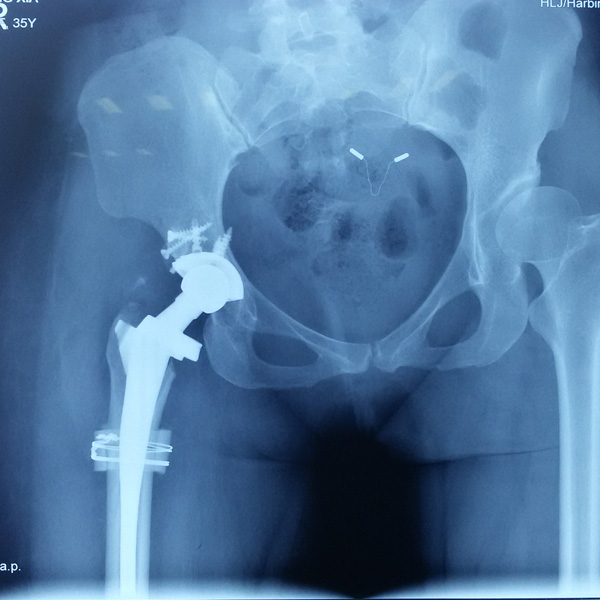

• 髖關節翻修髖關節翻修手術后手術前

髖關節翻修

患者蘇某,女性,11年前因“左髖關節屈曲攣縮畸形”行左側人工全髖關節置換,近來感覺左髖關節疼痛,不敢行走,經“攜生醫療平臺”就診于哈......

在線咨詢+更多詳情+